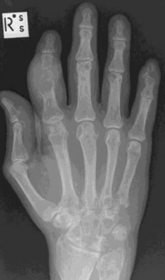

What disease is this? What indicates this? | Tophaceous gout. Soft tissue swelling surrounding the index finger PIPJ, with associated erosion and bone resorption |

What disease is this? | Tophaceous gout. |